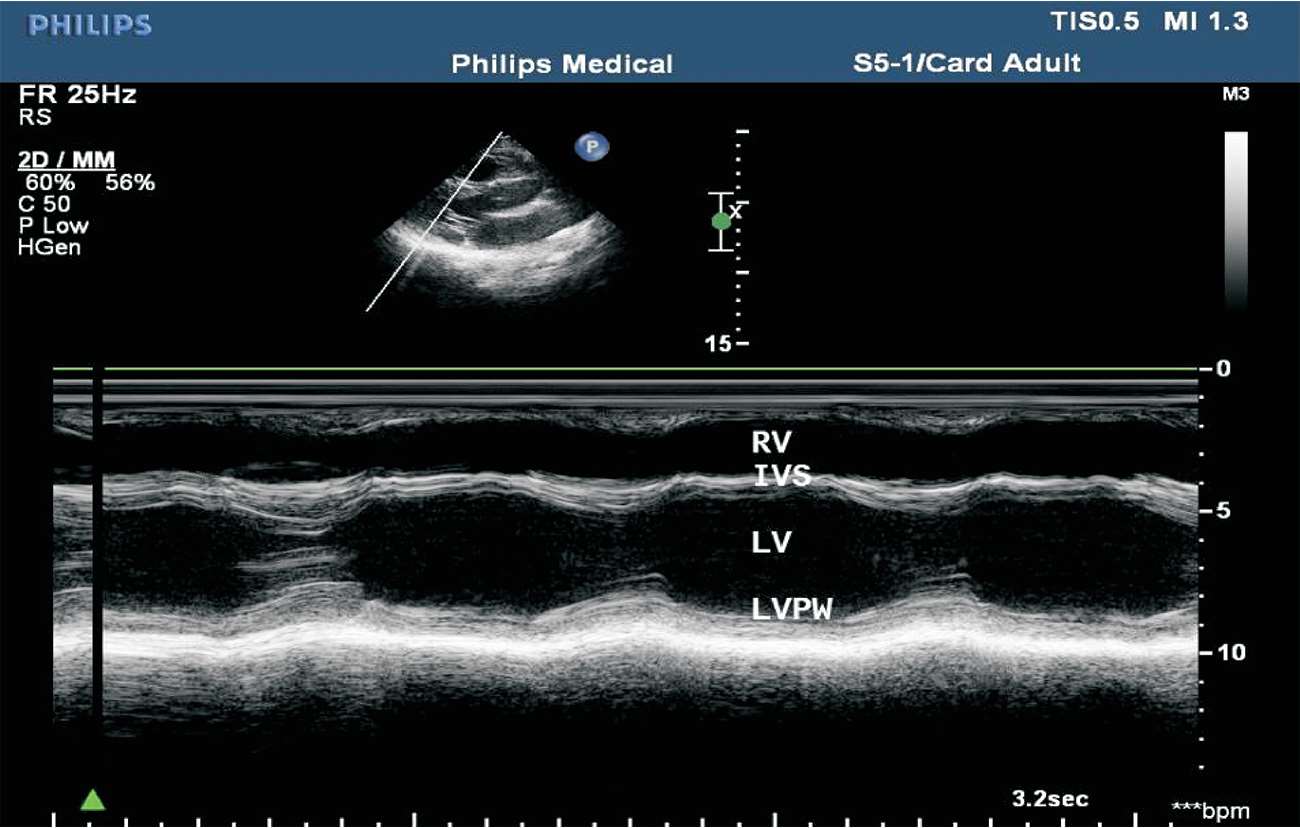

(1)胸骨旁左室长轴切面M型取样线置于二尖瓣腱索水平。

(2)结构从前到后依次为右室前壁、右心室、室间隔、左心室、左室后壁等。其中右心室大小及室间隔厚度应于舒张末期测量。可分别测量舒张末内径和收缩末内径以衡量左心室大小(见图1-24)。

图1-24 心室波群(RV:右心室;IVS:室间隔;LV:左心室;LVPW:左室后壁)